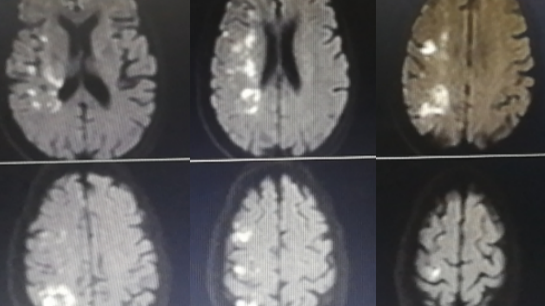

术后影像:

术后8天头颅CT及CTP影像:无出血,右侧半球脑灌注较术前明显改善。

术后1个月,电话随访,患者已经下地扶拐杖行走。mRs评分由术前的5分降低至2-3分。